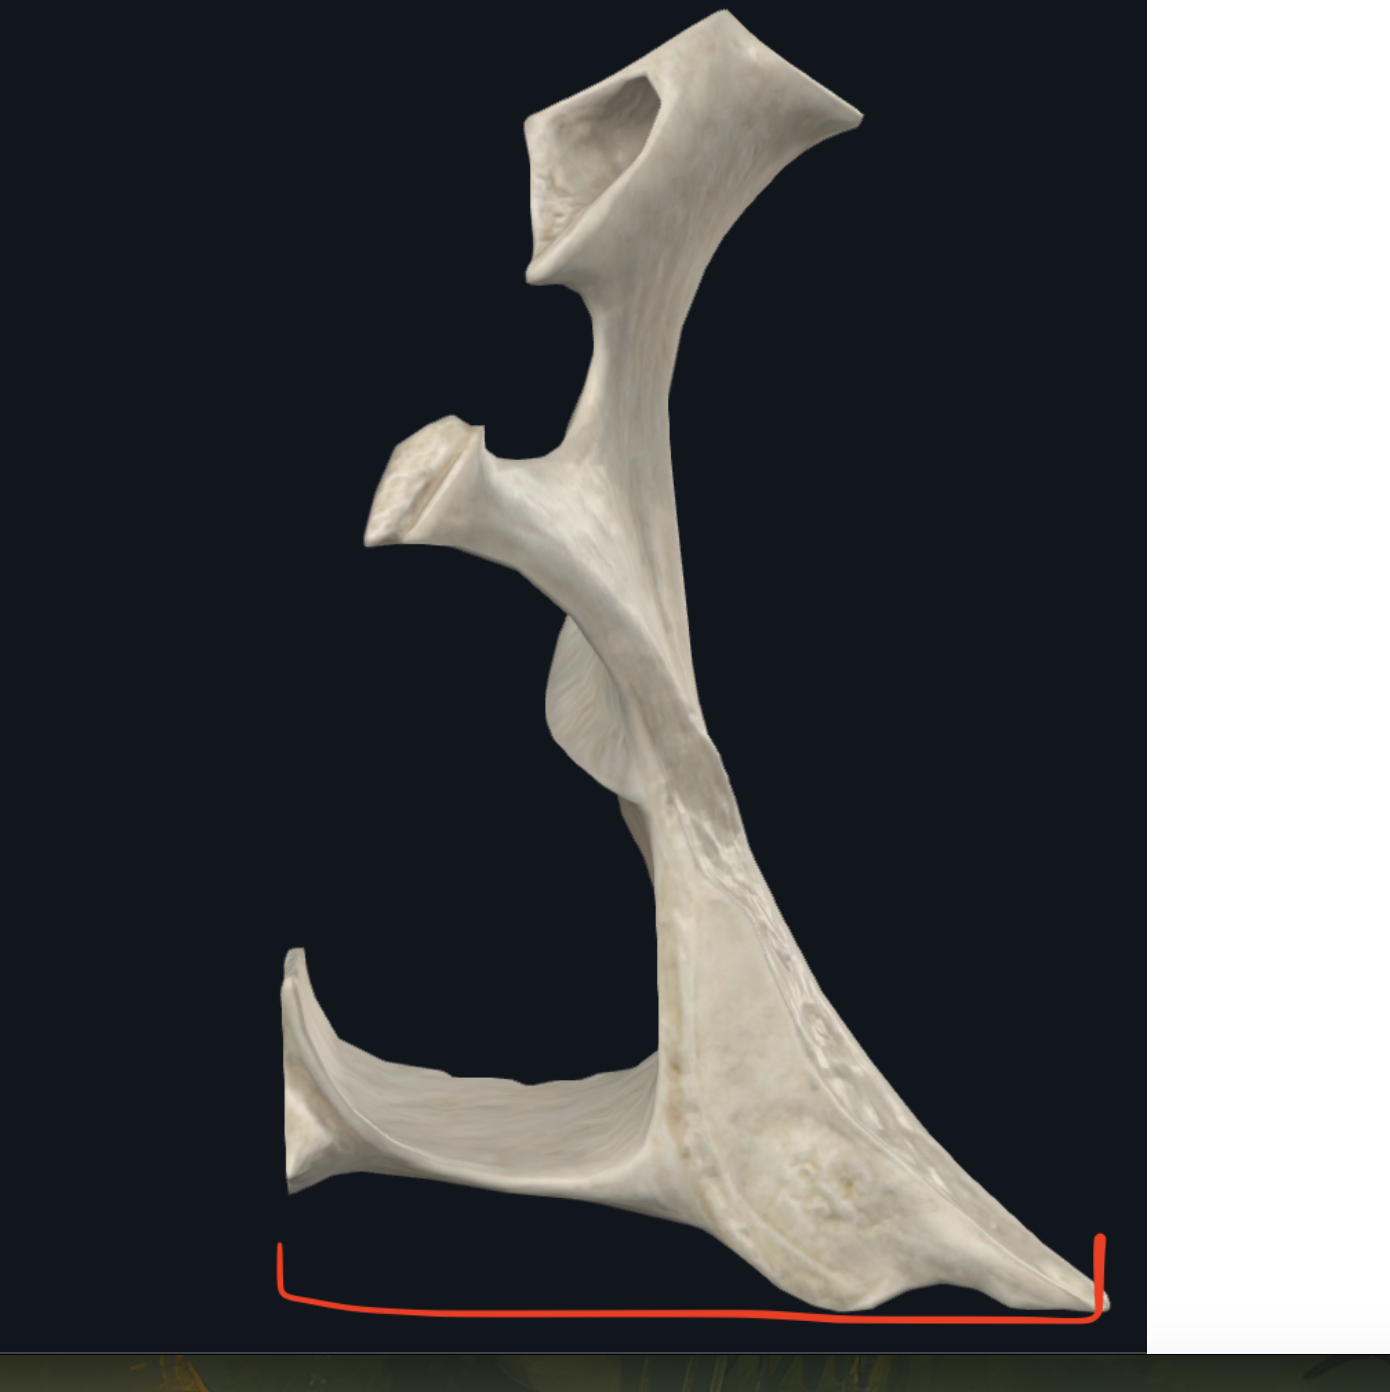

Mandíbula

Cuerpo Mandibular

Ramas mandibulares

Ángulo maxilar

Une el borde inferior con el borde posterior

o Gonión

Apófisis condilar

Se puede semidislocar

Dividido en cabeza y cuello

Apófisis coronoides

Músculo temporal

Escotadura sigmoidea

Fosa retromolar

tambien llamado triangulo o trígono